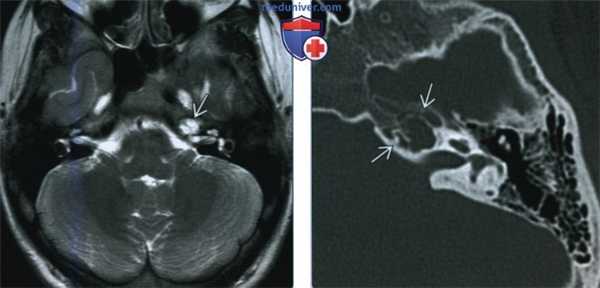

(Слева) При аксиальной МРТ Т2ВИ определяется подозрительный гиперинтенсивный участок в вершине пирамиды слева (МРТ выполнена по поводу потери сознания у пациента). Рентгенолог предположил холестериновую гранулему и назначил КТ височных костей для дообследования.

(Справа) При аксиальной КТ в костном окне у этого же пациента определяется снижение пневматизации ячеек в вершине пирамиды слева без признаков вздутия или разрушения трабекул. Было сделано заключение о «запертой» жидкости, не требующей наблюдения.